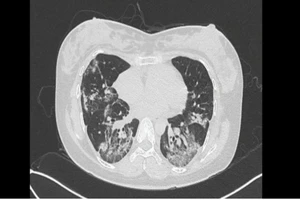

Hậu COVID-19, người phụ nữ 30 tuổi chưa đi nổi 10 bước oxy đã giảm 10%